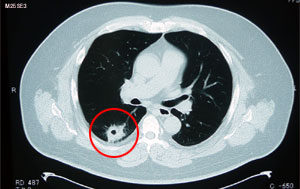

症例報告 モノリス虫草-症例報告(スマホで画像拡大可能です) 症例1 52歳 男性 右肺腺癌、胸膜、心膜浸潤、縦隔リンパ節転移、脳、骨転移 写真左:広範囲に転移が拡がっている。 写真右:3ヶ月後改善。体力・食欲回復、気力も出てきた。 症例2 86歳 女性 右肺上葉肺癌 未治療 写真左:広範囲に転移が拡がっている。 写真右:3ヶ月後改善。体力・食欲回復が回復しQOL回線を実感。 症...

症例報告 がん症例報告(スマホで画像拡大可能です 症例1 52歳 男性 右肺腺癌、胸膜、心膜浸潤、縦隔リンパ節転移、脳、骨転移 写真左:広範囲に転移が拡がっている。 写真右:3ヶ月後改善。体力・食欲回復、気力も出てきた。 症例2 86歳 女性 右肺上葉肺癌 未治療 写真左:広範囲に転移が拡がっている。 写真右:3ヶ月後改善。体力・食欲回復が回復しQOL回線を実感。 ...